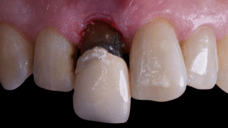

The surgical protocol began with the atraumatic extraction of tooth 1.1 to preserve as much of the alveolar socket as possible. Immediately following extraction, an N1 implant was placed into the socket using a guided surgical approach to ensure ideal three-dimensional positioning. The “one abutment one time” technique was applied to minimize soft tissue manipulation during the healing phase, which is particularly important in esthetic areas.

On the same day as the surgery, an immediate-load provisional crown was delivered. This restoration was fabricated in acrylic resin and screw-retained on the implant, following the “one abutment one time” principle. The provisional crown was carefully adjusted to avoid occlusal loading while supporting the peri-implant soft tissue architecture during the healing phase.